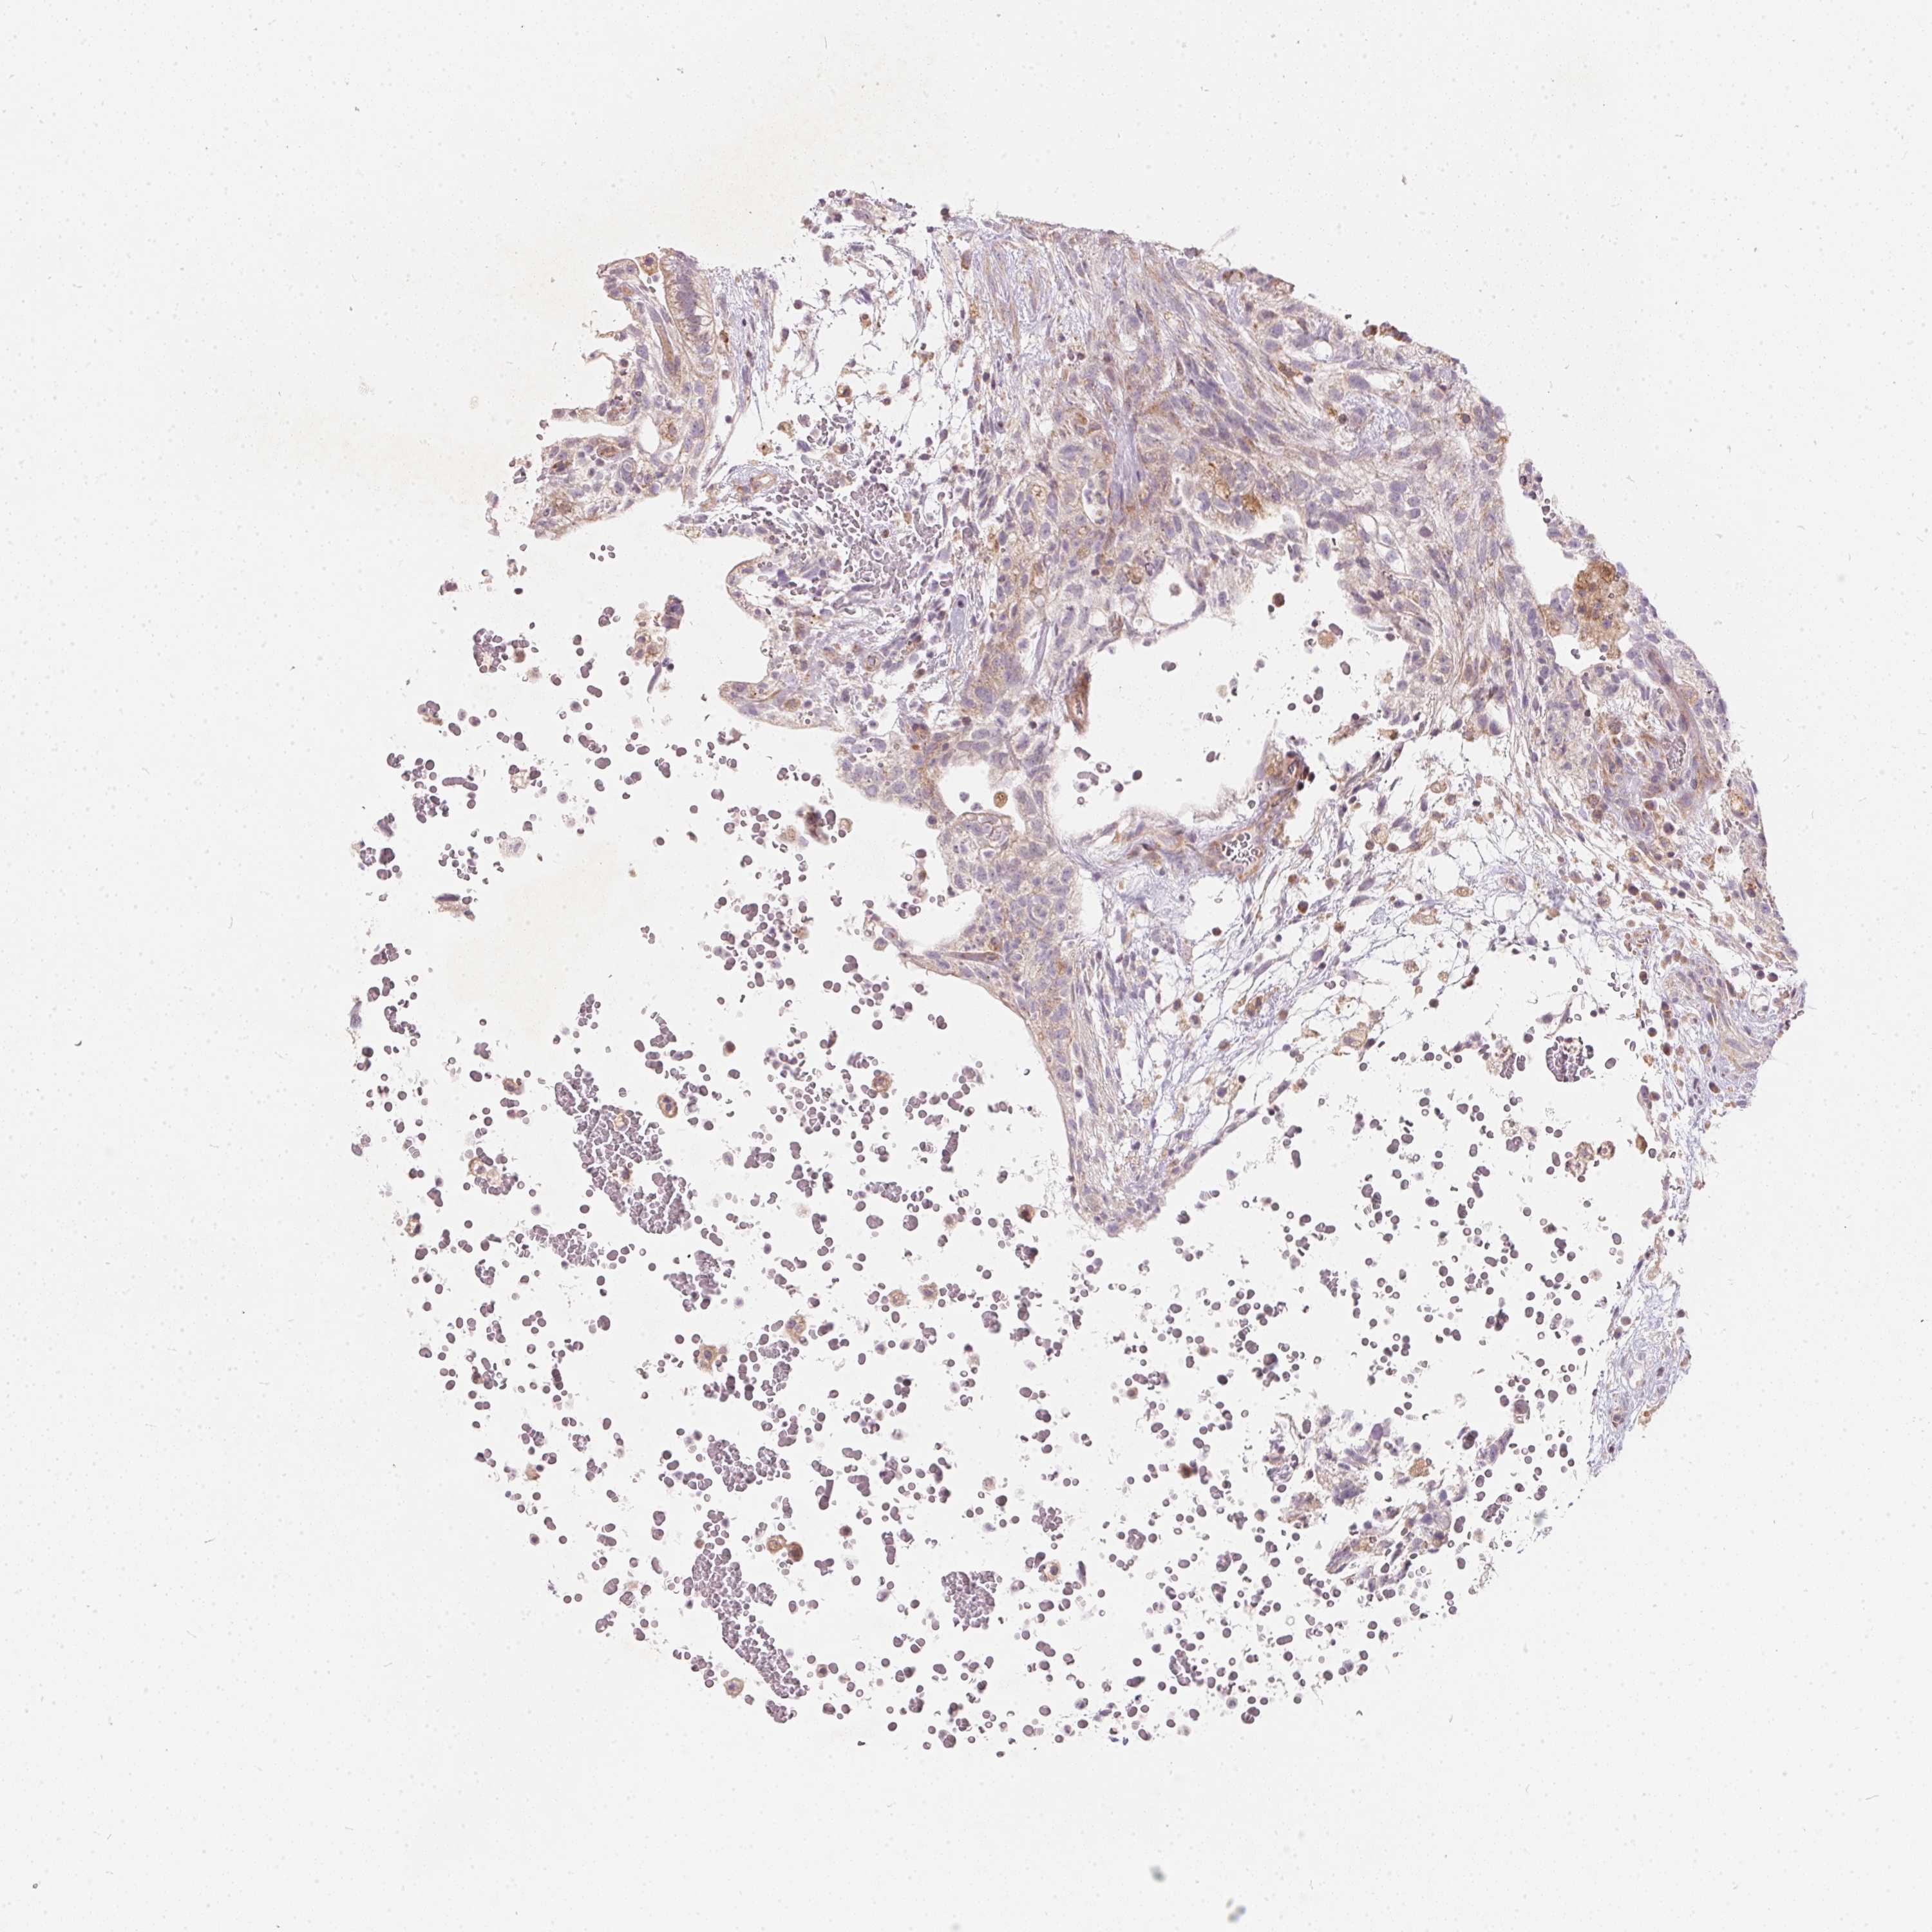

TESTIS CANCER - Protein expressioni

A mouse-over function shows sample information and annotation data. Click on an image to view it in a full screen mode. Samples can be filtered based on level of antibody staining by selecting one or several of the following categories: high, medium, low and not detected. The assay and annotation is described here.

Note that samples used for immunohistochemistry by the Human Protein Atlas do not correspond to samples in the TCGA dataset.

Antibody stainingi

Antibody staining in the annotated cell types in the current human tissue is reported as not detected, low, medium, or high, based on conventional immunohistochemistry profiling in selected tissues. This score is based on the combination of the staining intensity and fraction of stained cells.

Each image is clickable and will lead to virtual microscopy that enables deeper exploration of all samples and also displays staining intensity scores, fraction scores and subcellular localization as well as patient and tissue information for each sample.

Antibody HPA036823

Antibody HPA036824

Antibody HPA061412

Seminoma, NOS